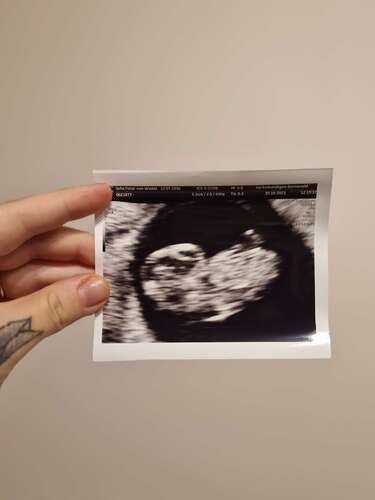

Gisteren 31-10 met 7+3 weken een uitwendige echo 😍